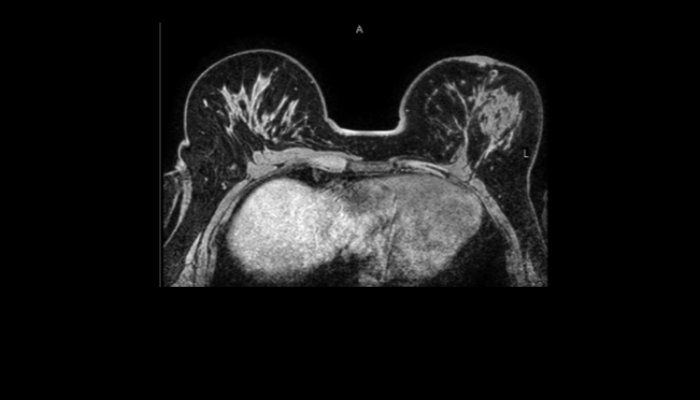

頭部MRI画像 頭部MRI脳腫瘍や脳梗塞、認知症など脳の病気を詳細に評価します。 MRA画像 頭部MRA造影剤を使わずに脳の動脈を描出します。動脈瘤や狭窄を検索します。 脊椎MRI画像 脊椎MRI椎間板ヘルニアや脊柱管狭窄症など脊椎や脊髄の疾患を評価します。 腹部MRI画像 上腹部MRI・MRCP肝臓・胆のう・膵臓・腎臓などの上腹部の重要臓器を詳細に評価します。 乳房MRI画像 乳腺MRIマンモグラフィや超音波と併せて、乳がんを検索や病変の範囲を評価します。 前立腺MRI画像 前立腺MRI前立腺がんを検索します。PSA高値の方はまず前立腺MRIをお勧めします。 子宮・卵巣MRI画像 子宮・卵巣子宮筋腫や子宮体癌、卵巣腫瘍など女性特有の病気を評価します。 膝関節MRI画像 膝関節膝関節の骨や靭帯、半月板を評価します。靭帯断裂や半月板損傷などレントゲンでは評価できない構造も診断できます。 肩関節MRI画像 肩関節肩関節の骨や腱、靭帯を評価します。腱板断裂や腱の断裂などレントゲンでは評価できない構造も診断できます。 心臓MRA 心臓MRA狭心症、心筋梗塞の原因となる冠動脈の狭窄を評価します。造影剤を使用せず、撮影可能です。 DWIBS画像 DWIBS全身のがんを広く検索します。リンパ節や転移の評価にも優れます。

乳腺MRI : Breast MRI

造影剤を使った乳腺の検査です

乳腺MRIの検査は造影剤を使用し、うつ伏せで行う検査です。

乳がんの検出感度が高く、マンモグラフィのような圧迫による痛みはありません。遺伝的に乳がんに罹りやすい方に有効的な検査です。